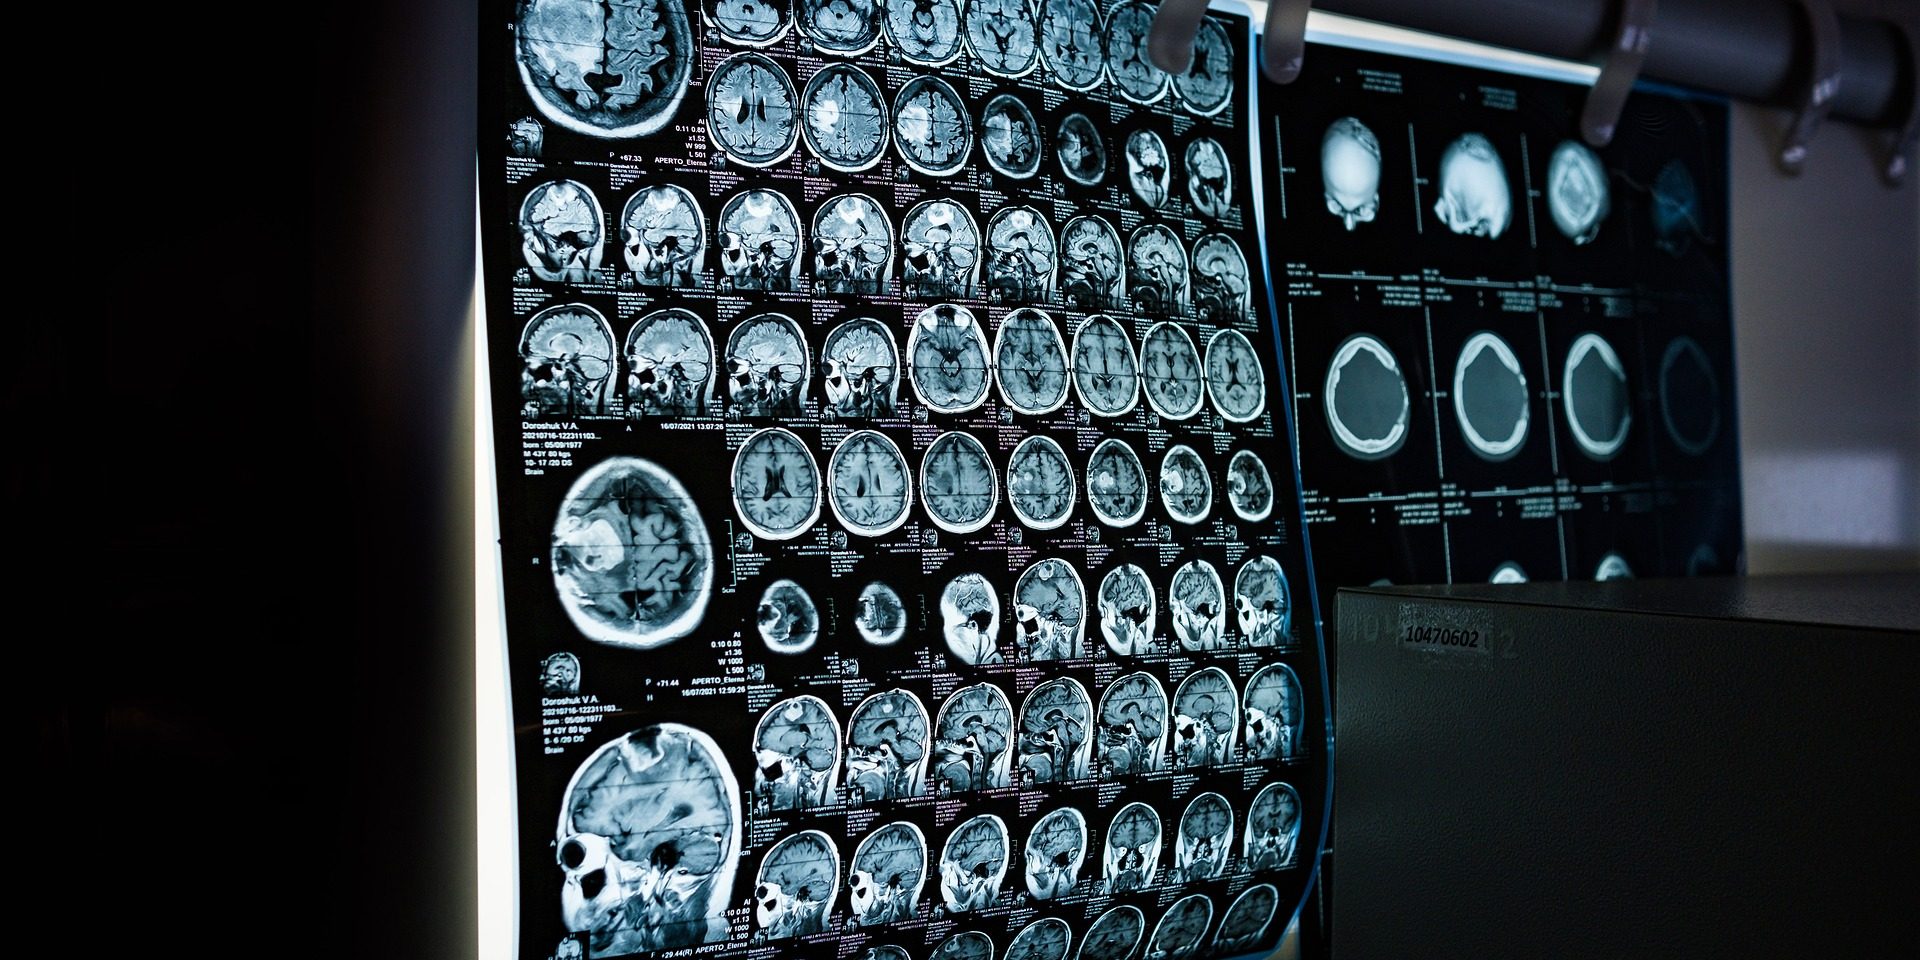

New research from the University of Alabama at Birmingham suggests some epileptic seizures can be predicted 30-45 minutes before they begin. The findings, published in NEJM Evidence, show that, for those with temporal lobe epilepsy, measuring brain activity in the thalamus through electroencephalography, or EEG, may be a reliable predictor of increased risk of seizures.